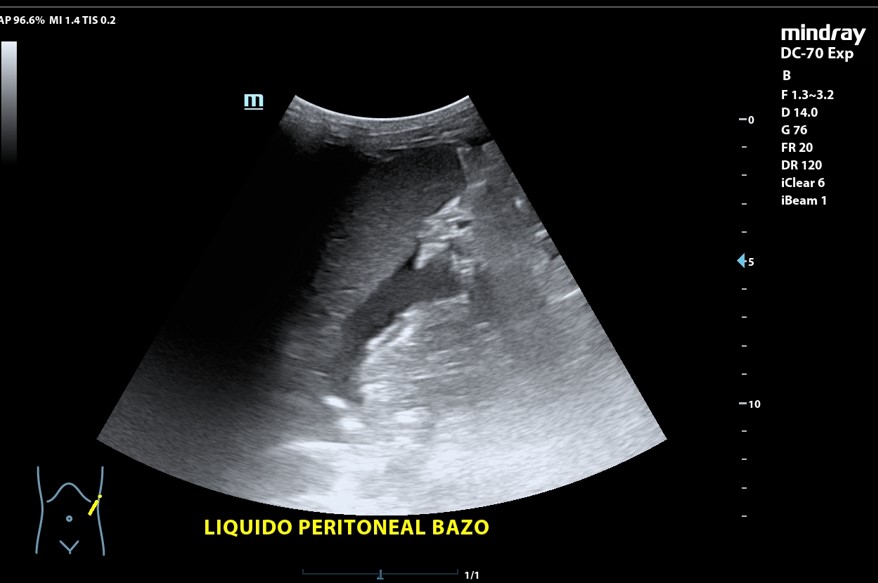

Presencia de 2 masas pélvicas bien delimitadas heterogéneas que captan Doppler, una de 5 cm de diámetro y otra ovalada de 10 cm de longitud. Líquido ascítico peritoneal, que también se observa alrededor del bazo y en espacio de Morrison. Derrame pleural derecho.